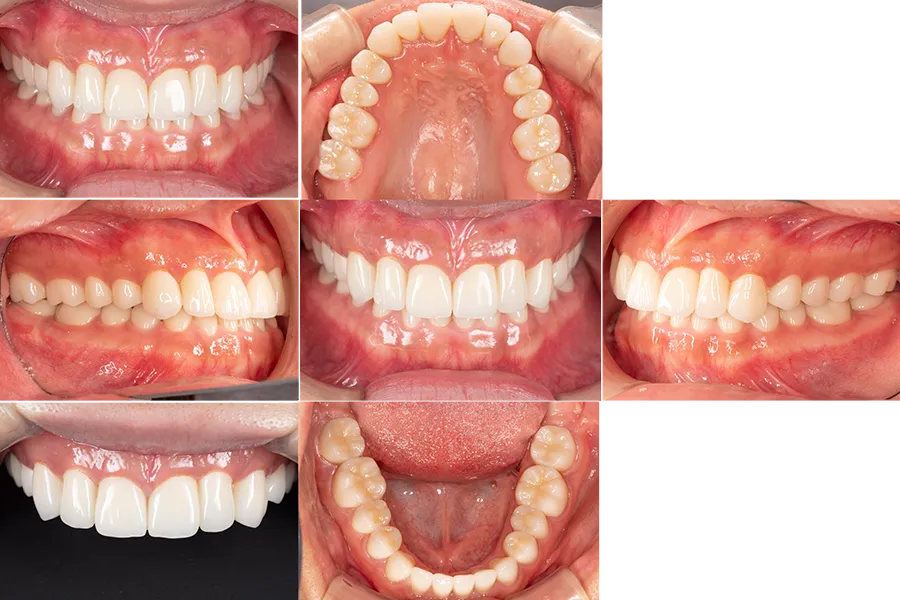

ジルコニアフレーム試適

最終補綴としてジルコニアフレームを使用したセラミッククラウンを製作しました。

口腔内で適合と咬合を確認し、(ジルコニア試適写真)問題がないことを確認してから最終装着を行いました。

治療後

全顎セラミッククラウンにより

- 咀嚼機能の回復

- 咬み合わせの安定

- 審美性の改善

が得られました。

セファロ分析による評価

本症例では治療前後でセファロ分析を行い、咬合高径の変化や顎顔面バランスの変化を評価しました。

術前にはやや下顎の前突傾向があった状態が咬合挙上により改善され、側貌が改善されています。